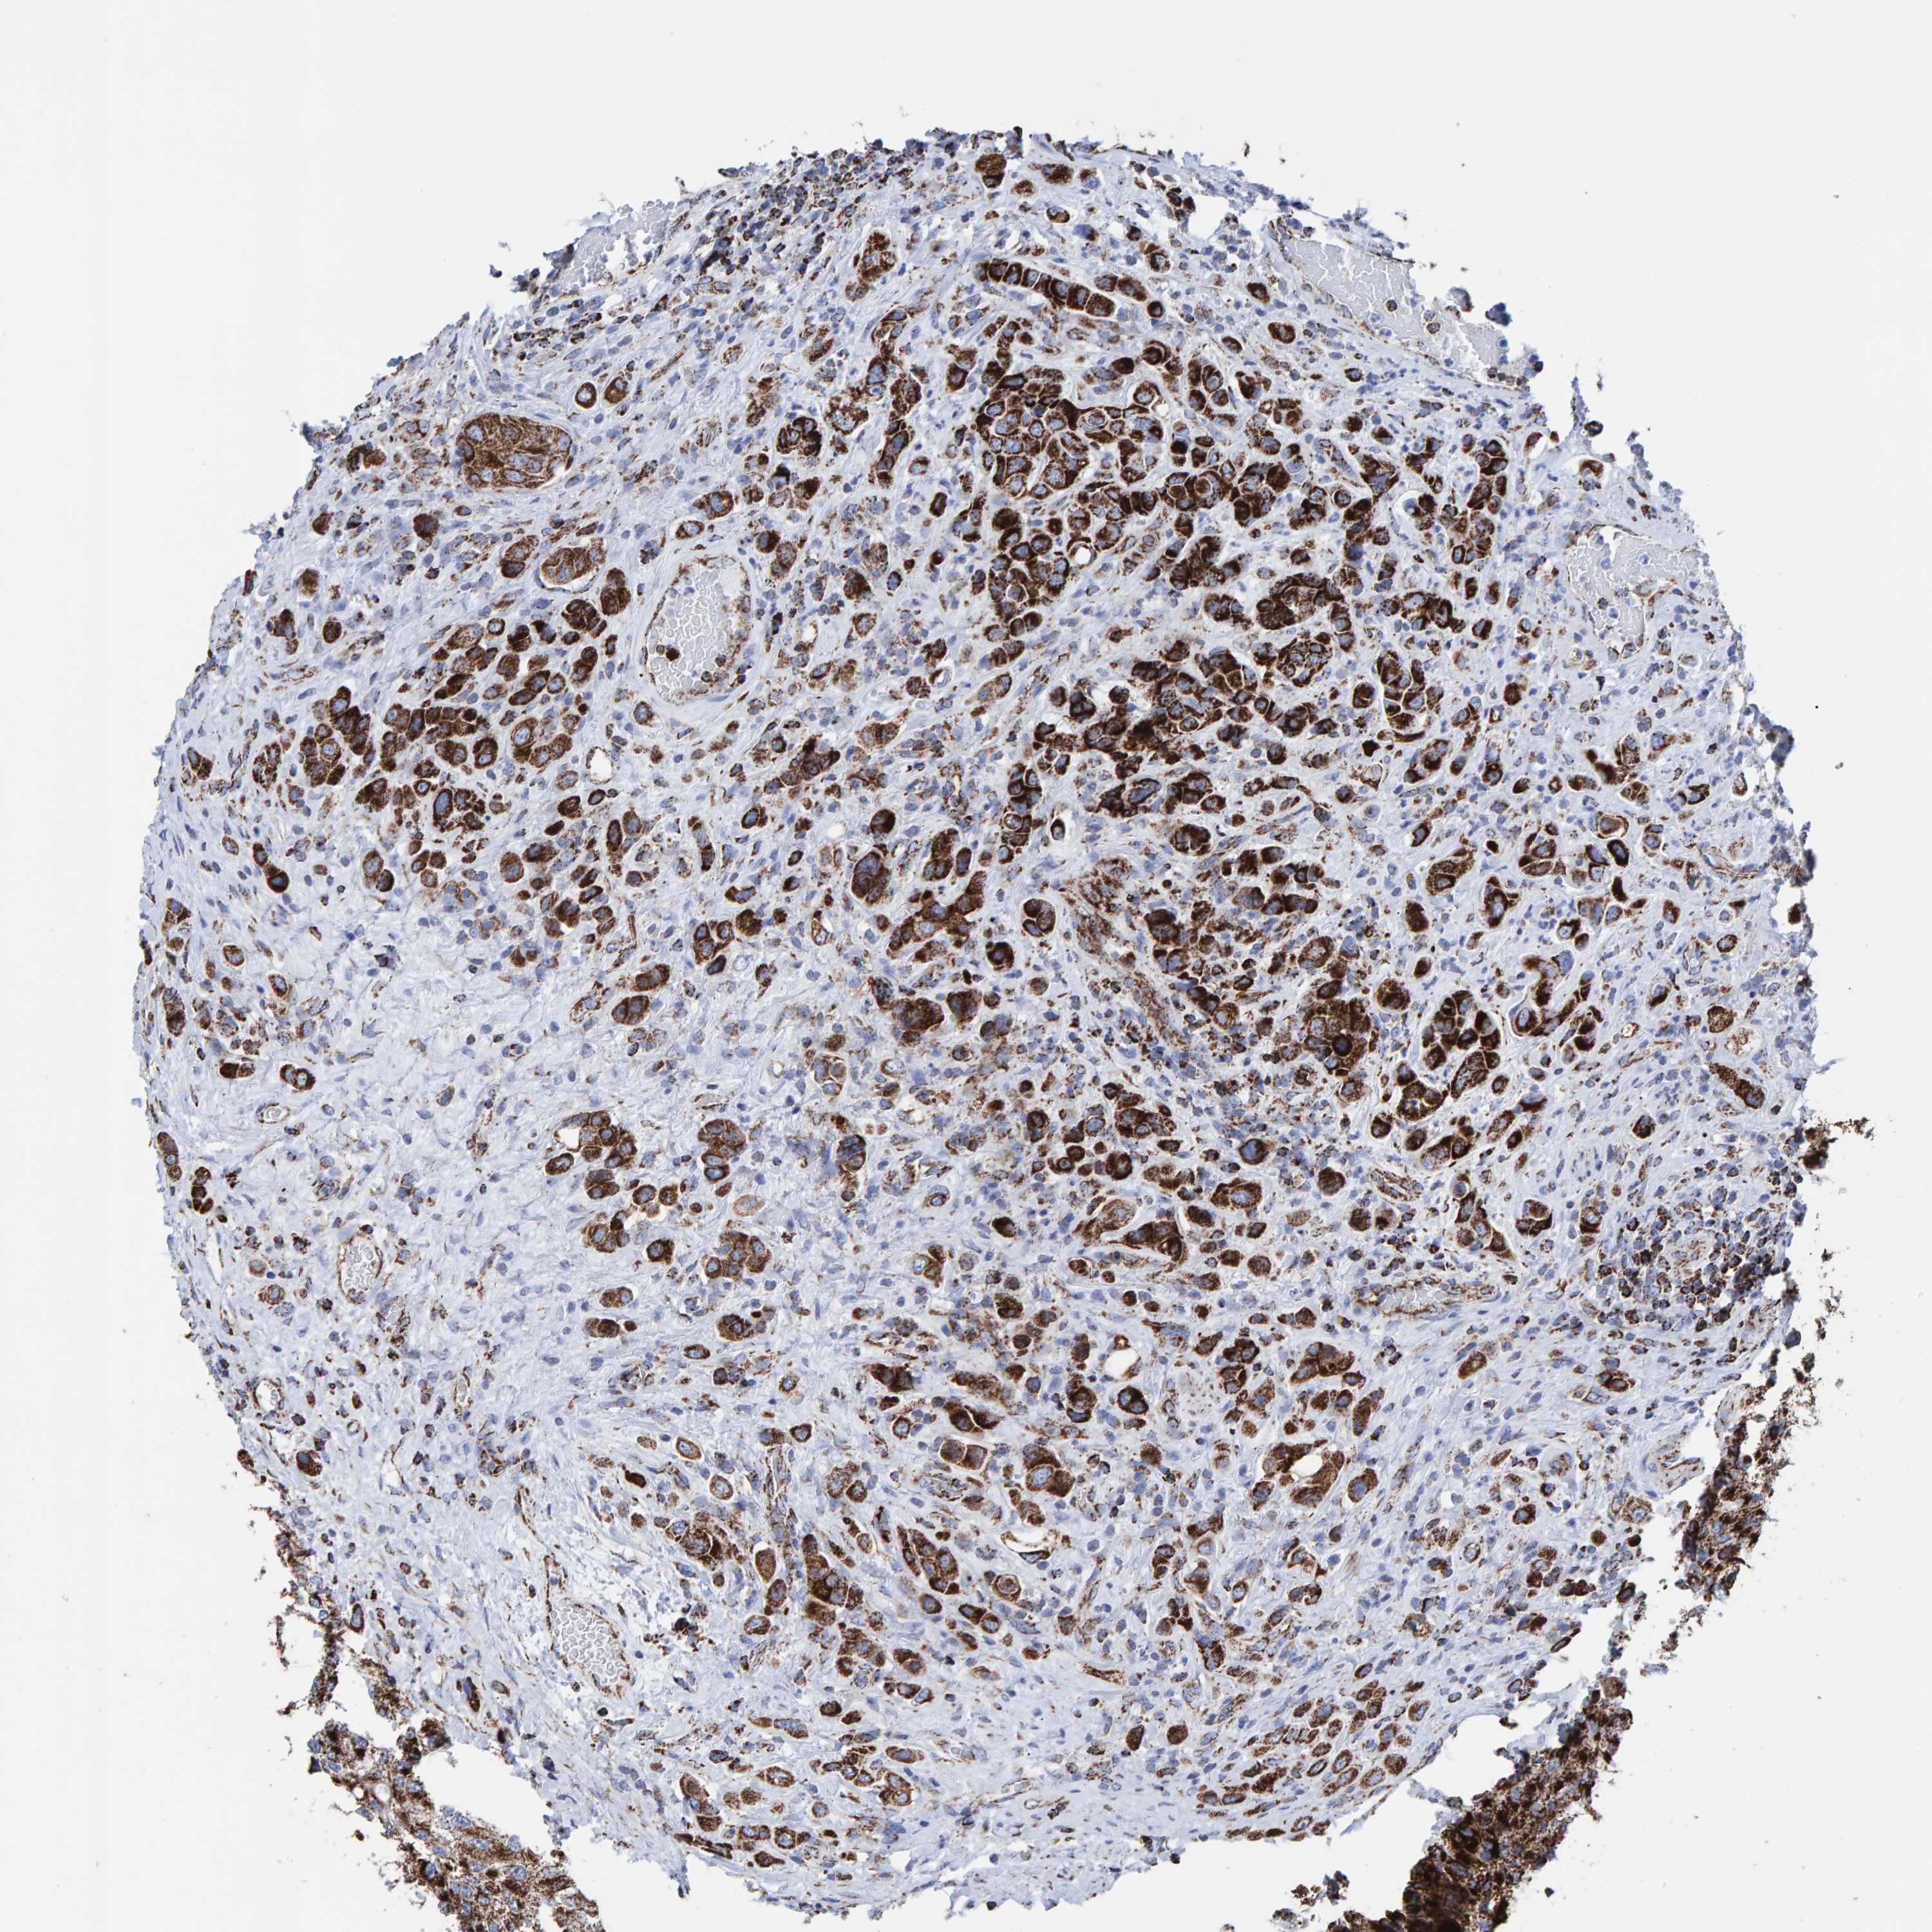

UROTHELIAL CANCER - Protein expressioni

A mouse-over function shows sample information and annotation data. Click on an image to view it in a full screen mode. Samples can be filtered based on level of antibody staining by selecting one or several of the following categories: high, medium, low and not detected. The assay and annotation is described here.

Note that samples used for immunohistochemistry by the Human Protein Atlas do not correspond to samples in the TCGA dataset.

Antibody stainingi

Antibody staining in the annotated cell types in the current human tissue is reported as not detected, low, medium, or high, based on conventional immunohistochemistry profiling in selected tissues. This score is based on the combination of the staining intensity and fraction of stained cells.

Each image is clickable and will lead to virtual microscopy that enables deeper exploration of all samples and also displays staining intensity scores, fraction scores and subcellular localization as well as patient and tissue information for each sample.

Antibody HPA022853

Antibody HPA023043

Antibody HPA023048

Staining

High

Medium

Low

Not detected

Intensity

Strong

Moderate

Weak

Negative

Quantity

>75%

75%-25%

<25%

None

Location

Nuclear

Cytoplasmic/membranous

Cytoplasmic/membranous,nuclear

Urothelial carcinoma, Low grade

Urothelial carcinoma, High grade